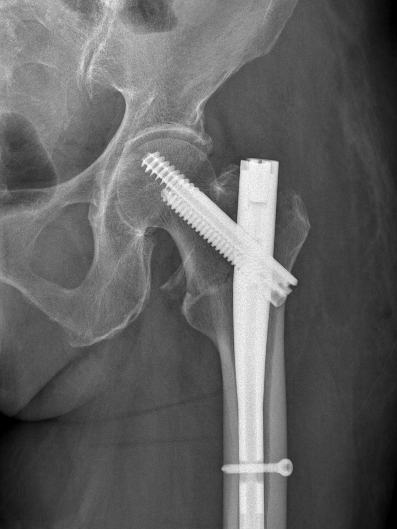

多年来,贵州航天医院各科室紧跟医学前沿,不断强技术、补短板,大力开展新技术、新项目,完成了许多高精尖、高难度、本地区“首例”的技术,填补了医院医疗技术空白,满足了群众日益增长的医疗需求。 贵州航天医院骨科率先在遵义地区开展骨搬移技术,截至目前,已治愈慢性骨髓炎、感染性骨不连、骨缺损、脉管炎、糖尿病足患者200余例,糖尿病足治疗保肢率达到98%。 本期,我们将为大家带来骨科特色技术——骨搬移技术(Ilizarov)。 案例分享 一名59岁的患者,身患糖尿病12年,在来我院3个月前出现了右脚溃烂的症状,来院就诊时,患者的右脚十分红肿,右脚脚趾坏死,伤口处不断流出黑红色脓液,情况十分严重。在接诊到患者时,骨科专家团队高度重视,立刻为患者完善了CT血管造影(CTA)等相关检查,诊断为:2型糖尿病,糖尿病周围血管病变,右糖尿病足。 术 前 考虑到患者情况比较严重,为最大限度保证患者肢体完整,科室专家团队进行了严格的讨论评估,为患者制定了骨搬移技术治疗方案,在征得患者及其家属的同意后,成功通过搬移骨块为患者进行治疗,促进患者病变肢体血管再生。 胫骨横向骨搬移外架固定 清除感染病灶 术后调节外架,通过搬移骨块 促进患肢血管再生 患者在术后三周前来换药,观察到感染得到进一步控制;术后六周复查,患者病变处已愈合,进行CT血管造影(CTA)后可明显观察到足部血管再生。 术后3周 术后6周愈合 CT血管造影见足部血管再生 糖尿病患者全身与局部的问题互为影响,形成恶性循环,糖尿病足溃疡创面迁延不愈,常见干性坏疽、湿性坏疽、趾坏死、深且大的溃疡以及骨髓炎等症状,还可导致脓毒血症,以往为保全生命,患者被迫选择一次或多次截肢。骨搬移技术的发展进步,能在血糖有效控制、局部有效清创下,有效促进患肢微血管再生,改善患肢血供,达到糖尿病足更快治疗康复的目的,并能根据病变情况最大限度的保障患者肢体完整。 什么是骨搬移技术 骨搬移技术是通过使用专用的骨外固定器固定骨段,每天缓慢牵拉,在牵拉搬移过程中,骨段尾部形成新骨及新的软组织,从而修复骨骼缺损及软组织缺损。是治疗大段骨缺损、骨不连、骨感染、肢体畸形的金标准方法,也用于治疗脉管炎、糖尿病足等肢体缺血性疾病。 骨感染缺损 切除感染段 搬移骨段 新骨形成 骨感染根治愈合 骨搬移技术原理 生物组织在持续、稳定、缓慢牵拉下,能刺激细胞分裂、组织再生,骨外固定技术运用该原理,通过持续缓慢调节外固定器形成牵拉张力,促进牵引成骨与相邻组织再生,如神经、血管、肌肉、皮肤等再生,达到治疗大段骨缺损、肢体缺血如糖尿病足等疾病的目的。 骨搬移技术优势 (一)除治疗骨缺损、骨不连外,有更广的适用范围,利用组织再生、血管再生等特性,能大量运用于肢体畸形的矫形、糖尿病足等的治疗。 (二)治疗效果确切,重建肢体外型和功能,极大降低截肢率和残疾率。 (三)明显提高了患者生活质量,极大减轻其家庭及社会负担。 肢体畸形的矫形 慢性骨髓炎 骨段切除 术后1年 濒临截肢的脉管炎术后6周 难愈创面术后3周 贵州航天医院骨科 专家团队 赵学平 骨科主任 主任医师 临床擅长:从事骨科临床工作30余年,对骨科常见疾病的诊治具有丰富的临床经验。 世界中医药联合会脊柱康复专业委员会常务理事,中华中医药学会整脊分会常务委员,中国中西医结合学会骨伤科分会肢体矫形功能重建与康复专家委员会常务委员,中国研究性医院学会骨科创新与转换专业委员会关节外科学组保髋工作委员会常委,中国康复技术转化及发展促进会骨外科与康复技术转化专业委员会常务委员,泛珠三角区域运动医学联盟(PPRD-SMA)理事会常务理事,中国研究型医院学会运动医学专业委员会委员,贵州省中医药学会整脊分会副主任委员,贵州省中西医结合学会银质针专业委员会副主任委员,贵州省康复医学会骨与关节专业委员会常务委员,贵州省人民医院骨科专科联盟常务理事,贵州省康复医学会骨内科专业委员会常务委员,中华医学会贵州省骨科学会委员,贵州省康复医学会脊柱脊髓专业委员会常务委员,贵州省运动医学分会委员,贵州省康复医学会骨与软组织肿瘤专业委员会委员,遵义市医学会创伤分会副主任委员,贵州省康复医学会骨内科专业委员会遵义地区分会常务委员,遵义市医疗事故鉴定、伤残鉴定、工伤鉴定、司法鉴定专家。 长期从事骨科临床研究及教学工作,在国家级、省部级杂志发表论文20余篇,SCI论文2篇,参与主编骨科专著2部,主持省部级科研项目2项,参与指导省部级、市级科研项目6项。 陈明勇 骨科副主任 副主任医师 临床擅长:从事创伤骨科工作约20年,对骨缺损、骨不连、骨肿瘤、肢体畸形等的肢体矫形重建及功能重建,慢性化脓性骨髓炎的根治治疗、糖尿病足的保肢治疗、快速康复理念(ERAS)下的老年骨折的诊治,四肢复杂骨折的诊治,四肢骨折等微创手术治疗具有丰富的临床经验。 2004年毕业于遵义医学院临床专业,曾在中国人民解放军总医院、广西医科大学第一附属医院、上海第六人民医院骨科进修。中国中西医结合学会骨伤科专业委员会横向骨搬移治疗糖尿病足及微血管网再生学组首届委员,遵义市医学会创伤分会常务委员。 瞿 辉 骨科 副主任医师 临床擅长:对骨科的常见病、关节外科、脊柱外科及运动医学疾病的诊治具有丰富的临床经验,熟练掌握骨科手术操作技术。 毕业于遵义医学院临床医学系,2005年前往广州中山大学第一附院骨显微医学部进修学习,2011年前往成都华西医院进修学习,并多次在省内外学习骨科相关知识,是中华医学会骨科分会会员。 赵兴东 骨科 主任医师 临床擅长:擅长骨科的常见病及各种创伤、四肢骨折创伤修复、骨感染、手足疾病的诊治和手足体表畸形的矫形整复,熟练掌握骨科四肢骨病及创伤的手术操作技术,尤其在四肢关节复杂性损伤、手足外伤、组织缺损创面、难治创面的皮瓣修复方面及平足、高弓足矫形方面及四肢慢性疼痛诊治、康复方面具有丰富的临床经验。 硕士研究生,毕业于遵义医学院临床外科系,2015年前往山东省立医院手足外科进修学习;遵义市医学分会创伤分会第一、二届委员,遵义市手外科医学会第二委届员会常务委员;在省级及省级以上期刊发表文章9篇,参编著作2部,参与主持并完成市级课题1项,参与市级课题2项、省级课题1项。 张俊凯 骨科 副主任医师 临床擅长:从事骨科临床工作28年,对创伤骨折、骨感染、骨缺损、骨不连等外科诊治,四肢骨折的微创手术治疗,四肢复杂骨折(如关节内粉碎性骨折、多发骨折等)的损伤控制及手术治疗等具有丰富的临床经验。 1995年毕业于遵义医学院临床专业,2009年前往复旦大学附属医院骨科进修1年。 卢懿明 骨科 副主任医师 临床擅长:从事骨科工作18年,对创伤骨折、四肢骨折的微创手术治疗、四肢复杂骨折(如关节内粉碎性骨折、多发骨折等)的损伤控制及手术治疗,尤其是髋部骨折的PFNA等微创技术,踝关节骨折、膝关节周围骨折的Mipo微创技术等具有丰富的临床经验,开展了4项新技术,发明6项新型专利技术。 2005年毕业于遵义医学院临床专业,2017年,前往南方医科大学第三附属医院骨科进修半年,回院后运用Mipo技术对骨干骨折及干骺端骨折的治疗技术,同时积极开展骨盆骨折、髋臼骨折腹直肌外侧切口的应用;发表了多篇专业论文,经常参与省内外学术交流会授课,获得医院荣誉称号多个。 邬夏荣 骨科 副主任医师 临床擅长:从事骨科工作16年,对四肢复杂骨折、骨肿瘤的诊治,尤其是足踝创伤、慢性踝关节损伤、平足症等诊疗具有丰富的临床经验。 2006年毕业于遵义医科大学临床医学专业,曾在陆军军医大学西南医院进修学习,发表多篇骨科学术论文。 余德怀 骨科 副主任医师 临床擅长:从事骨科工作10余年,对运动医学、骨关节、脊柱外科常见病、多发病的诊治具有丰富的临床经验。 硕士研究生,2011年毕业于遵义医学院临床医学专业,曾前往遵义医科大学附属医院运动医学专业进修学习;是贵州省医学会运动医学分会青年委员,西部关节镜联盟委员;发表多篇骨科学术论文。 冯 乾 骨科 副主任医师 临床擅长:从事骨科工作近20年,熟练掌握骨科多发病及常见病的诊治,尤其对脊柱退变性疾病的诊断及治疗具有丰富的临床经验,主要研究脊柱微创相关治疗方式,能熟练开展椎间孔镜及VBE。 曾前往北京大学第三医院进修学习疼痛及椎间孔镜、首都医科大学友谊医院专业进修脊柱内镜;是贵州省康复医学会第三届脊柱脊髓专业委员会委员;发明专利3项、发表脊柱外科专业论文多篇。 张艳金 骨科 副主任医师 临床擅长:从事骨外科工作16年,对复合伤、多发伤的救治、四肢骨干骨折、关节周围骨折、骨肿瘤、骨髓炎等诊治具有丰富的临床经验。 中共党员,硕士研究生,2006年本科毕业于山西医科大学第二临床医学院,2011年研究生毕业于北京军区总医院;在“老年COPD患者合并髋部骨折的诊治”国际合作课题组研究两年,在老年髋部骨折的诊治方面具有丰富的经验,并发表论文6篇;承担遵义市级课题1项;承担遵义医科大学的临床教学工作,获得遵义医科大学优秀带教老师荣誉。编撰有《骨科疾病诊疗精粹》一书,开展2项新技术,编撰地方规范《务川自治县创伤骨科常见疾病诊疗规范》一书。 赵小锋 骨科 副主任医师 临床擅长:从事骨科临床工作11年,对骨科常见病、多发病诊疗有较为丰富的临床经验,擅长脊柱相关疾病诊断及治疗,尤其是颈、腰、腿疼痛疾病诊断及治疗,擅长胸腰椎骨折微创经皮穿刺内固定术、经皮穿刺椎体成形术、经皮穿刺脊柱内镜下腰椎间盘摘除术、单纯开创腰椎间盘摘除术、腰椎滑脱复位椎间植骨椎融合内固定术、腰椎管狭窄减压融合内固定术及人工髋、膝关节置换术等。 2012年毕业于遵义医学院外科学专业硕士研究生,2019年参加“遵义市115医学人才精英计划”于上海交通大学第一附属医院培训学习,2023年于北京大学第三人民医院脊柱外科进修学习,曾获得遵义市优秀医师荣誉称号。 遵义市手外科第一届委员,遵义市医学会创伤分会第一届委员,遵义市医学会创伤分会第二届委员,贵州省康复医学会第三届脊柱脊髓专业会委员,遵义市医学会烧伤与整形外科学分会委员,发表论文5篇,其中国家级核心期刊1篇,SCI论文1篇,主持市级课题1项并结题,参与市级课题2项。 贵州航天医院骨科简介 基本情况 贵州航天医院(原3417医院)骨科组建于1968年,前身是以创伤和断肢(断指)再植闻名于世的上海市第六人民医院骨科,中国断肢(断指)再植的奠基者、中科院院士陈仲伟等著名专家、学者多次莅临科室指导医疗、教,是贵州省最早拥有专业骨科技术科室之一,在70年代开展了贵州省首例断肢(断指)再植手术。组建50余年来,诊治患者已逾百万,挽救了无数的伤病员,成为了保障遵义地区人民群众健康的重要支撑。 经过几代人的不懈努力,今天的骨科,已由创伤骨科发展至骨病、骨肿瘤、骨结核等领域,现有脊柱外科、关节外科、四肢创伤、手足外科四个亚专科,成为了集医疗、教学、科研于一体的综合学科,是贵州省临床重点专科、遵义市临床重点专科、遵义市骨科临床医学中心、遵义市基层骨科专科联盟理事长单位。 科室目前开放床位110张,共有医护人员50余人,副高级以上专家18人,硕士研究生15人。拥有一流骨科医疗设备多台,每年不定期选派优秀技术骨干到全国各大知名医学院校进修、学习、参观、交流,并邀请国内、国外知名专家教授来院进行交流、指导,通过不断引进国内外先进的诊疗技术,科室医疗技术水平稳步提升,为广大人民群众提供了优质的医疗服务。 专科特色 骨一科 (一)骨缺损、骨不连的肢体与功能重建 胫骨横向骨搬移技术治疗糖尿病足: (二)慢性骨髓炎的根治治疗 (三)肢体缺血性疾病如糖尿病足、脉管炎的保肢治疗 (四)皮瓣修复 (五)复杂创伤的治疗 (六)老年髋部骨折及小儿骨折快速手术 老年髋部骨折: 骨二科 (一)胸腰椎骨折微创经皮椎弓根螺钉固定术 (二)老年性骨质疏松性患者腰椎滑脱脊柱内固定术(骨水泥螺钉) (三)V形双通道脊柱内镜技术(VBE)腰椎融合术治疗腰椎退行性疾病 (四)老年性骨质疏松性骨折(PVP/PKP)术 (五)人工髋关节置换术 (六)双侧股骨头坏死人工全髋关节置换 (七)右侧全髋置换术后假体周围骨折翻修 (八)人工膝关节置换术 (九)人工膝关节假体松动翻修 (十)关节镜技术 传统手术切口 关节镜技术切口 诊疗范围 骨一科 1.四肢创伤、矫形。 2.手、足踝外科。 骨二科